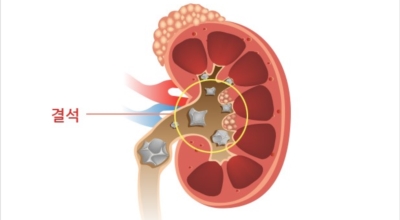

요로결석이란

수분 섭취 감소는 요로결석의 가장 중요한 발병 이유가 되는 것 이라고 합니다. 수분의 섭취가 떨어지면 요석결정이 소변에 머무르는 시간이 길어져 요석형성이 증가하게 되며 요로결석의 발생은 유전적인 소인이 있다는 것이 정설이나 후천적인 생활습관도 관련성을 보입니다.